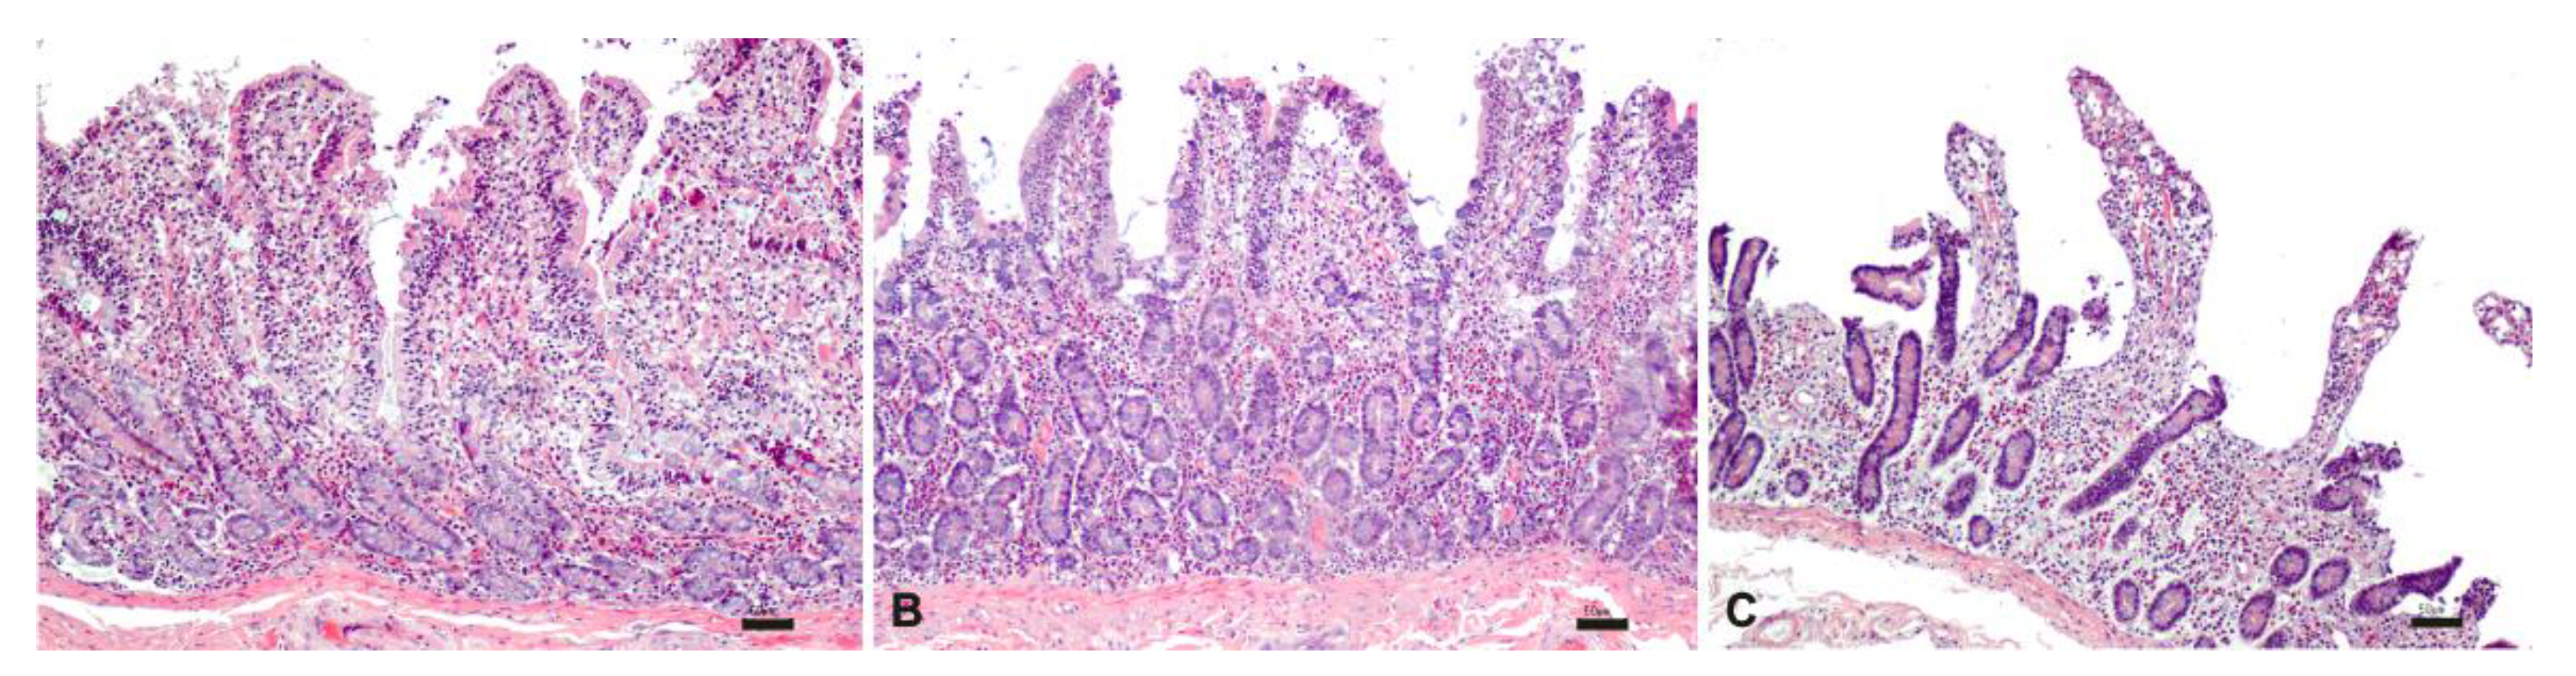

Unlike what was observed in the samples stored at room temperature, the samples stored at 37 °C were histologically characterized by diffuse morphological alterations starting from 2 h, indicating a lower stability of the intestine at higher temperatures (Figure 8).

Figure 8.

Histological evaluation of intestinal tissue stored at 37°C at 1 h (A), 2 h (B) and 3 h (C). HE; bar: 50 µm.